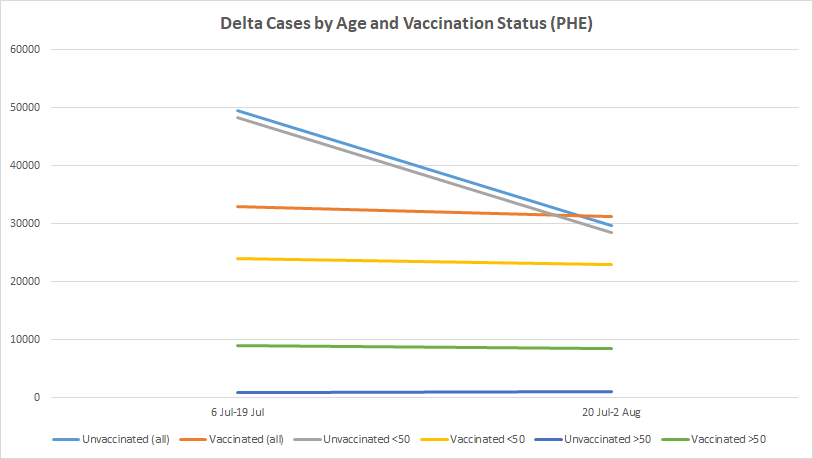

PHE Data Confirms That New Infections Peaked and Dropped in the Unvaccinated Before They Did in the Vaccinated

Back in July, ZOE data showed cases in the unvaccinated falling while they climbed in the vaccinated, but this disappeared when they updated their methodology. New data from PHE suggests they were right first time.